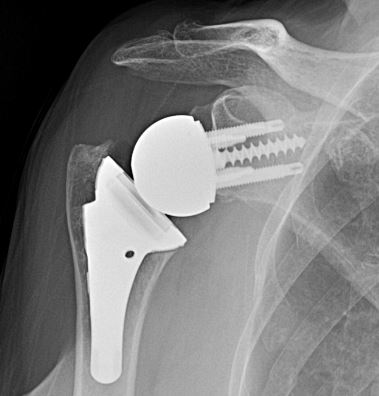

Reverse Shoulder Replacement

Reverse shoulder replacement reverses the anatomy, and the ball is replaced with a socket, likewise; the socket is replaced with a ball (glenosphere).